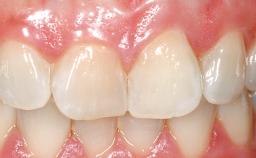

Late Placement of an Implant in a Maxillary Left Central Incisor Site

A 30-year-old female patient had lost tooth 21 and was referred to our clinic for consultation and treatment. Due to advanced apical infection, tooth 21 had been extracted two months earlier at another clinic and an acrylic-resin tooth had been bonded to the adjacent teeth. The patient desired implant treatment to avoid any damage to the adjacent natural teeth. While the patient had no history of any systemic disorder, she was a heavy smoker and exhibited medium to advanced periodontitis in the entire jaw. After the initial treatment to achieve a pocket probing depth of less than 4 mm and no bleeding on probing, a decrease in the height of the papillae mesial and distal to the extraction site and overall gingival recession were observed.

Abutment Type CAD/CAM

Prosthesis Type FDP

SAC Level Complex

Defining Characteristics One missing tooth to be replaced by an implant-borne crown

Esthetic Risk High

Provisional Implant-Supported Prosthesis Prosthodontic margin < 3 mm apical to mucosal margin Prosthodontic margin < 3 mm apical to mucosal margin